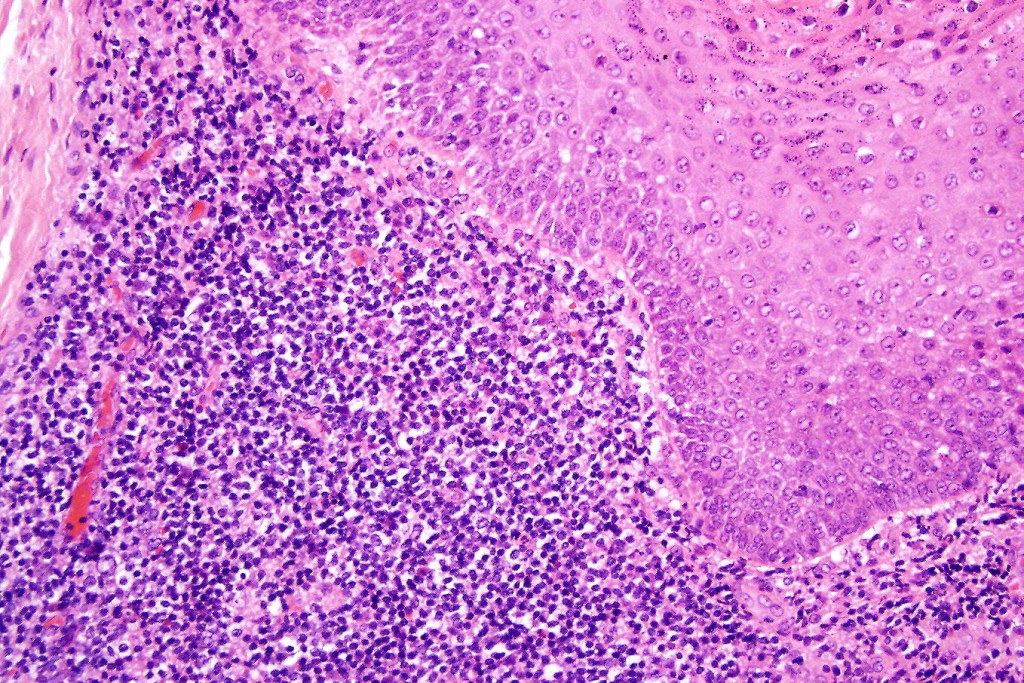

Histological features

•Follicular infiltration by atypical lymphocytes & Sézary cells

•Large cell transformation occasionally present